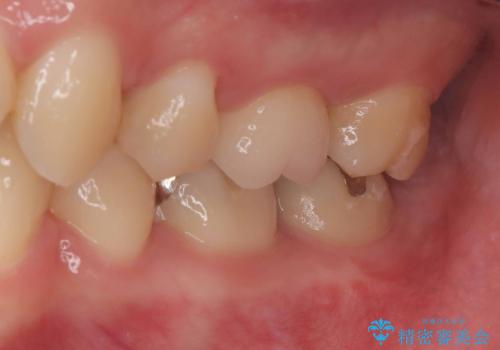

矯正治療も当院で行ったので、矯正治療終了後オールセラミッククラウンで治療を行いました。

汚染されている神経は除去し残りの神経を残すためVPTを行いバイオセラミックのバイオシーシーラーで充填しオールセラミッククラウンで治療を行いました。治療後2年経過しましたが、神経は温存され経過は良好です。